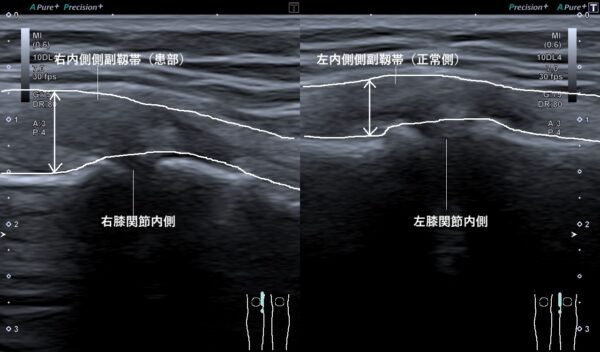

超音波画像検査を行うと右内側側副靱帯が腫れていました(画像、矢印の長さの比較)。

内側側副靱帯は膝関節の内側を補強し、膝関節の外反(関節内側が開く動き)や外旋(関節を外側に捻る動き)を強力に制御する働きがあります。

しかし、瞬間的に捻挫などの大きな力が加わると、靱帯の強度を超えてしまうため、靱帯が過度に引き伸ばされて損傷し、出血や組織液貯留によって腫れてしまいます。